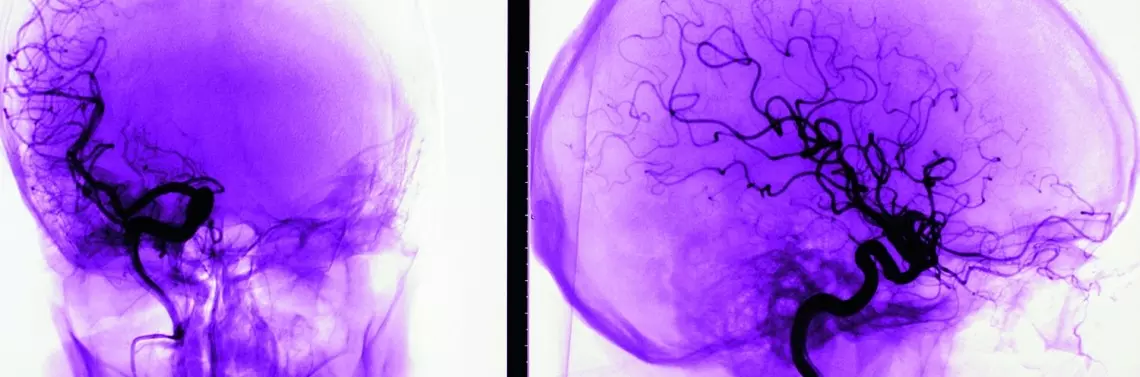

Neurofibromatoza typu 2 (NF2) to genetyczny zespół predysponujący do zmian nowotworowych w obrębie układu nerwowego. Jest dziedziczona autosomalnie dominująco. Przyczyną choroby jest mutacja genu na 22. chromosomie. U osób dotkniętych tym schorzeniem rozwijają się nerwiaki osłonkowe (schwannoma) na nerwach przedsionkowych, co prowadzi do zaburzeń słuchu, a w niektórych przypadkach nawet do głuchoty. Guzy mogą występować również na innych nerwach czaszkowych, a także na korzeniach nerwów rdzeniowych i nerwach obwodowych [1, 2].

Obraz kliniczny NF2 jest odmienny u dzieci i u dorosłych. U pacjentów pediatrycznych najczęściej rozpoznaje się zaćmę (60–80% przypadków), schwannoma nerwu przedsionkowego (43%), oponiaki i guzy rdzenia (31%), schwannoma skóry (8%), opadanie stopy spowodowane obwodową neuropatią (3%) i mononeuropatię twarzową (19%).